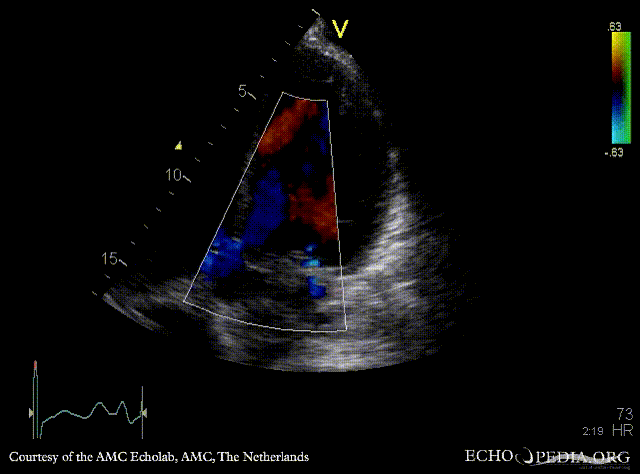

E00181.jpg

E00182.gif

M-Mode through aortic valve PLAX: Color Doppler signal shows severe aortic regurgitation